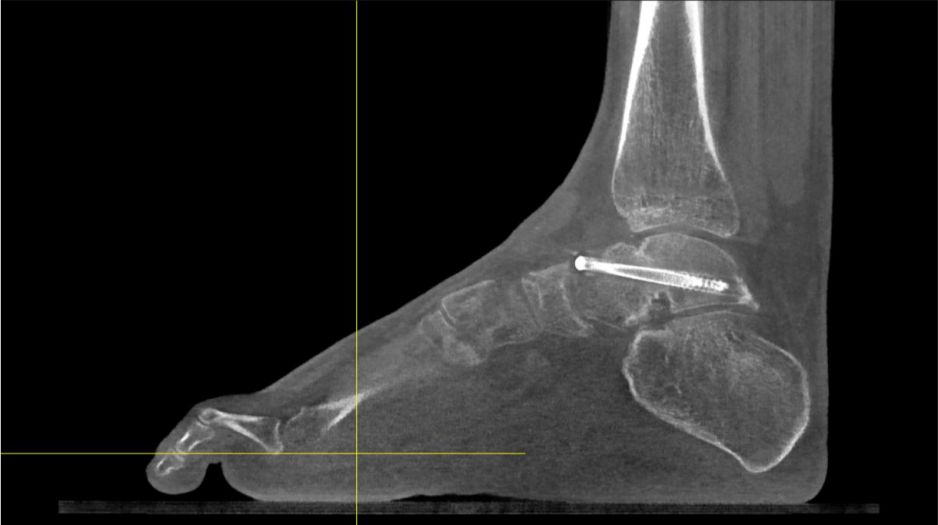

Das pedCAT ist die erste Praxislösung eines digitalen Volumentomografen ( englisch: Conebeam) für den Fuss- und Sprunggelenk Chirurgen. Das Gerät ermöglicht die Diagnostik mit Hilfe eines pyramidenförmigen Röhrenstrahles und eines Flachbilddetektors, die sich 360° um den Patienten drehen und sowohl belastete als auch teilbelastete Untersuchungen von Fuss- und Sprunggelenken zulassen. Innerhalb von 68 Sek. ist die Untersuchung von beiden Füssen abgeschlossen, die Bildrekonstruktion erfolgt in 3,5 Minuten.